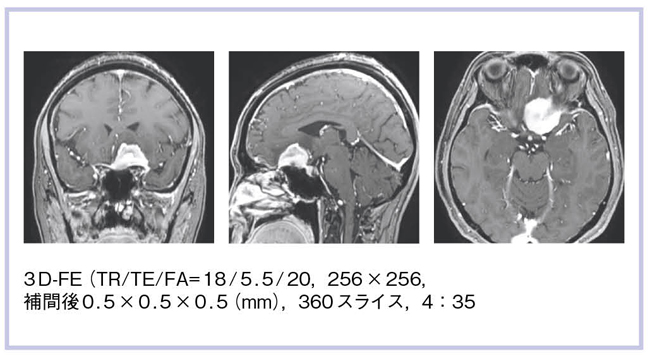

また当院では,3Tの造影T1強調画像は基本的に2Dスキャンで撮像しているが,高いSNRを応用して3Dスキャンも行っている。図5は,傍鞍部髄膜腫の症例であるが,脳全体を4分35秒で撮像でき,特に限局性の病変では,ターゲットを絞った再構成が可能となる。今後,さまざまな症例で,どのようにルーチン化していくかは検討が必要である。

図5 傍鞍部髄膜腫の3D-FE画像